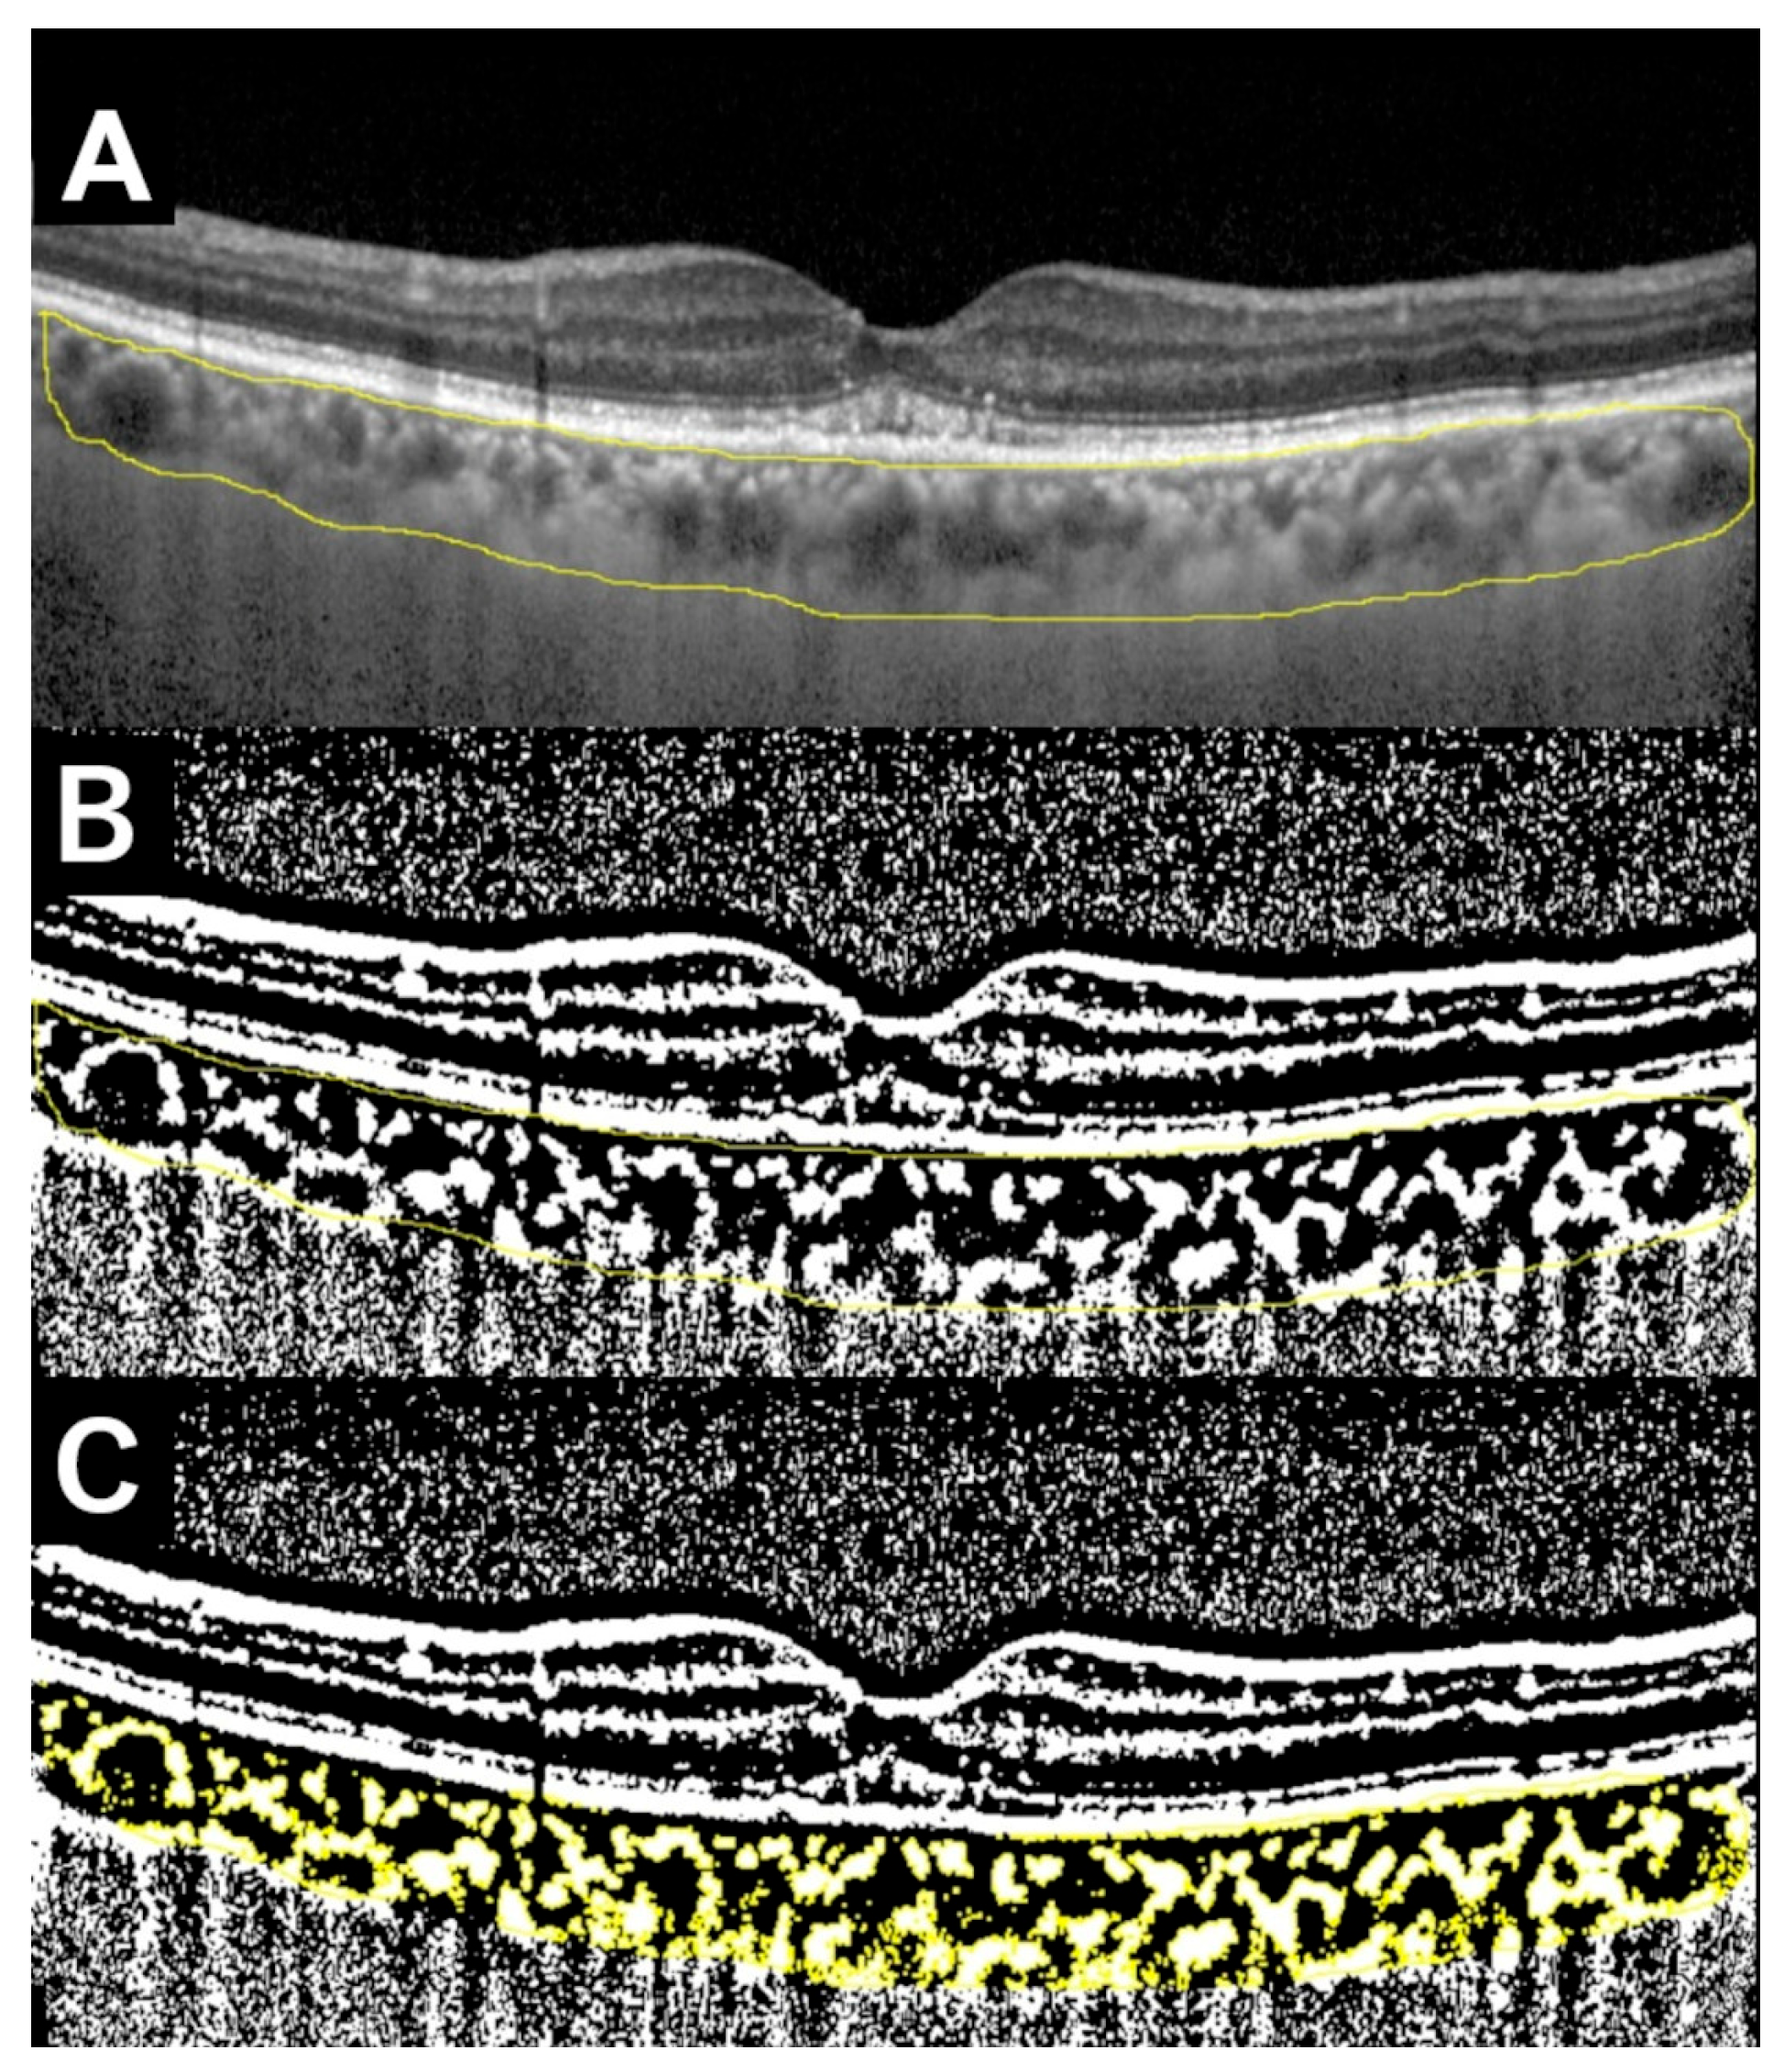

Evaluation of Choroidal Structure in Type 1 Macular Neovascularization Using Different Optical Coherence Tomography Analyses: Scale Bar and Binarization

- Sonoda, S.; Sakamoto, T.; Yamashita, T.; Shirasawa, M.; Uchino, E.; Terasaki, H.; Tomita, M. Choroidal structure in normal eyes and after photodynamic therapy determined by binarization of optical coherence tomographic images. Investig. Ophthalmol. Vis. Sci. 2014, 55, 3893–3899. [Google Scholar] [CrossRef]

- Iovino, C.; Pellegrini, M.; Bernabei, F.; Borrelli, E.; Sacconi, R.; Govetto, A.; Vagge, A.; Di Zazzo, A.; Forlini, M.; Finocchio, L.; et al. Choroidal vascularity index: An in-depth analysis of this novel optical coherence tomography parameter. J. Clin. Med. 2020, 9, 595. [Google Scholar] [CrossRef] [PubMed]